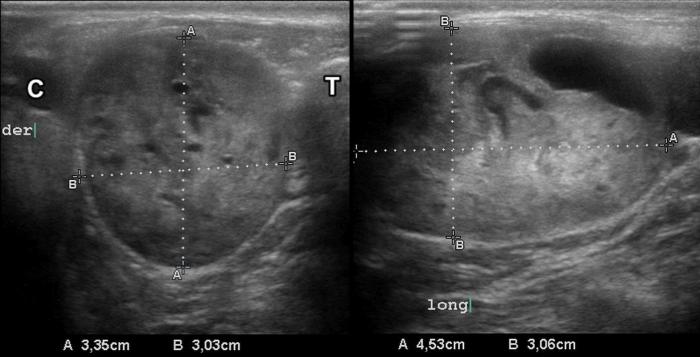

El hipertiroidismo felino, endocrinopatía común en gatos geriátricos, se caracteriza por una hipertrofia glandular funcional, frecuentemente bilateral, aunque puede presentarse en forma asimétrica o unilobular17. Los hallazgos ecográficos incluyen aumento del tamaño tiroideo, contornos irregulares, parénquima hipo o mixto-ecogénico, y pérdida de la arquitectura homogénea (Figura 12A-B), con lesiones cavitarias internas (Fgura 13A-D). Es común observar nódulos de pequeño tamaño (<10 mm), bien delimitados y con vascularización periférica o central aumentada al Doppler color9.

Los estudios de seguimiento postratamiento han evidenciado una reducción significativa del volumen glandular tras terapias con metimazol o radioyodo, observándose una reaparición progresiva de la homogeneidad parenquimatosa en algunos casos10. Sin embargo, en gatos con recaídas clínicas o mala respuesta, la glándula puede mantener un patrón nodular persistente o desarrollar mineralización distrófica19.

Las neoplasias tiroideas son menos frecuentes en gatos que en perros y, cuando ocurren, suelen corresponder a adenomas funcionales. No obstante, se han documentado casos de carcinomas, los cuales pueden imitar ecográficamente al patrón nodular benigno, aunque con mayor tendencia a la invasión local, pérdida de la cápsula y vascularización desorganizada13 (Figura 14). Por ello, la ecografía debe ser interpretada junto con los hallazgos clínicos, bioquímicos y eventualmente citológicos.